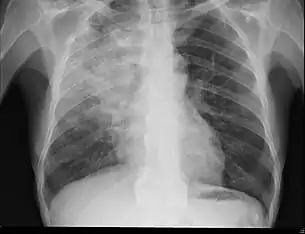

Radiography is the most common form of imaging used in the initial assessment of a foreign body presentation. Most patients receive a chest x-ray to determine the location of the foreign body.[2] Lateral neck, chest, and bilateral decubitus end-expiratory chest x-rays should be obtained in patients suspected of having aspirated a foreign body.[6] However, the presence of normal findings on chest radiography should not rule out foreign body aspiration as not all objects can be visualized.[2] In fact, up to 50% of cases can have normal findings on radiography.[7] This is because visibility of an object depends on many factors, such as the object's material, size, anatomic location and surrounding structures, as well as the patient's body habitus.[13] X-ray beams only show an object if that object's composition blocks the rays from traveling through, making it radiopaque and appearing lighter or white on the image. This also requires it to not be stuck behind something that blocks the beams first.[13] Objects that are radiopaque include items made of most metals except aluminum, bones except most fish bones, and glass. If the material does not block the x-ray beams it is considered radiolucent and will appear dark which prevents visualization.[13] This includes material such as most plastics, most fish bones, wood, and most aluminum objects.[13]

Signs on x-ray that are more commonly seen than the object itself and can be indicative of foreign body aspiration include visualization of the foreign body or hyperinflation of the affected lung.[13] Other x-ray findings that can be seen with foreign body aspiration include obstructive emphysema, atelectasis, and consolidation.[8]

While, x-ray can be used to visualize the location and identity of a foreign body, rigid bronchoscopy under general anesthesia is the gold-standard for diagnosis since the foreign body can be visualized and removed with this intervention.[2] Rigid bronchoscopy is indicated when two of the three following criteria are met: report of foreign body aspiration by the patient or a witness, abnormal lung exam findings, or abnormal chest x-ray findings.[2]